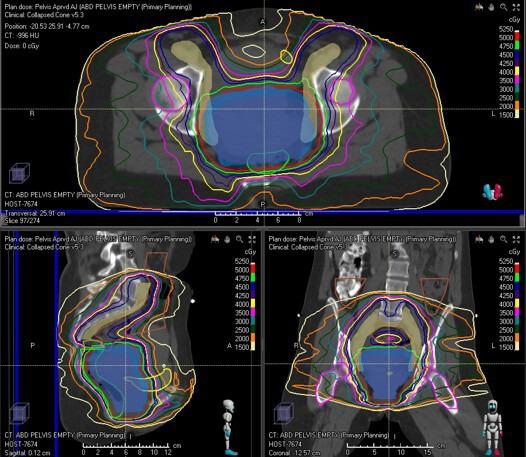

Vaginal cancer is a rare cancer. A lot of the data used in the treatment of this cancer are extrapolated from cervical cancer data. Radiation therapy plays a significant role in the treatment of vaginal cancer. The advances in radiation therapy in both external beam and brachytherapy have improved local control, survival, and toxicity. Brachytherapy plays an important role in treating vaginal cancer, but treatment should be individualized to each tumor. Imaging, particularly magnetic resonance imaging, plays an essential role in the management of patients with vaginal cancer, from diagnosis to staging to treatment management to surveillance.